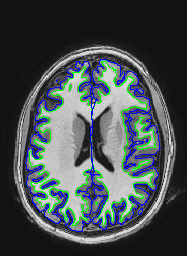

EPI images are significantly distorted relative to true brain anatomy. This is a problem because activation maps created from EPI images are overlaid on T1 images (or cortical surface models created from T1 images) which reflect the true anatomy. The following images show a T1 image with outlines for the outer boundary of gray matter (blue line) and white matter (green line).

Here are uncorrected EPI images with the same boundaries overlaid.

A qualitative way of judging the effectiveness is to overlay the unwarped EPI on the T1 and see how they match. Here are corrected EPI images with the gray and white matter boundaries overlaid.